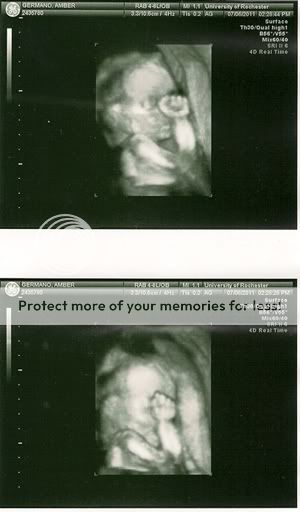

Also, monthly checkup went great! Blood pressure is perfect, fundal height is measuring EXACTLY along with my weeks, and heartbeat sounds good. I went for a follow-up ultrasound to check on her enlarged kidney, and both kidneys got smaller already! It was unlikely that they were going to change much after two weeks, but the doctors needed to make sure that they at least weren't getting significantly bigger. Now I have to go back at 32 weeks for one more ultrasound to determine if she will need to be monitored after birth.

I had an imaging ninja for an ultrasonographer. She switched to the 3D probe without any warning whatsoever. Which is dangerous, because I think 3D is creepy and without knowing what she was doing it almost gave me a heart attack. (Call me a traditionalist, but 2D is the way to go.)